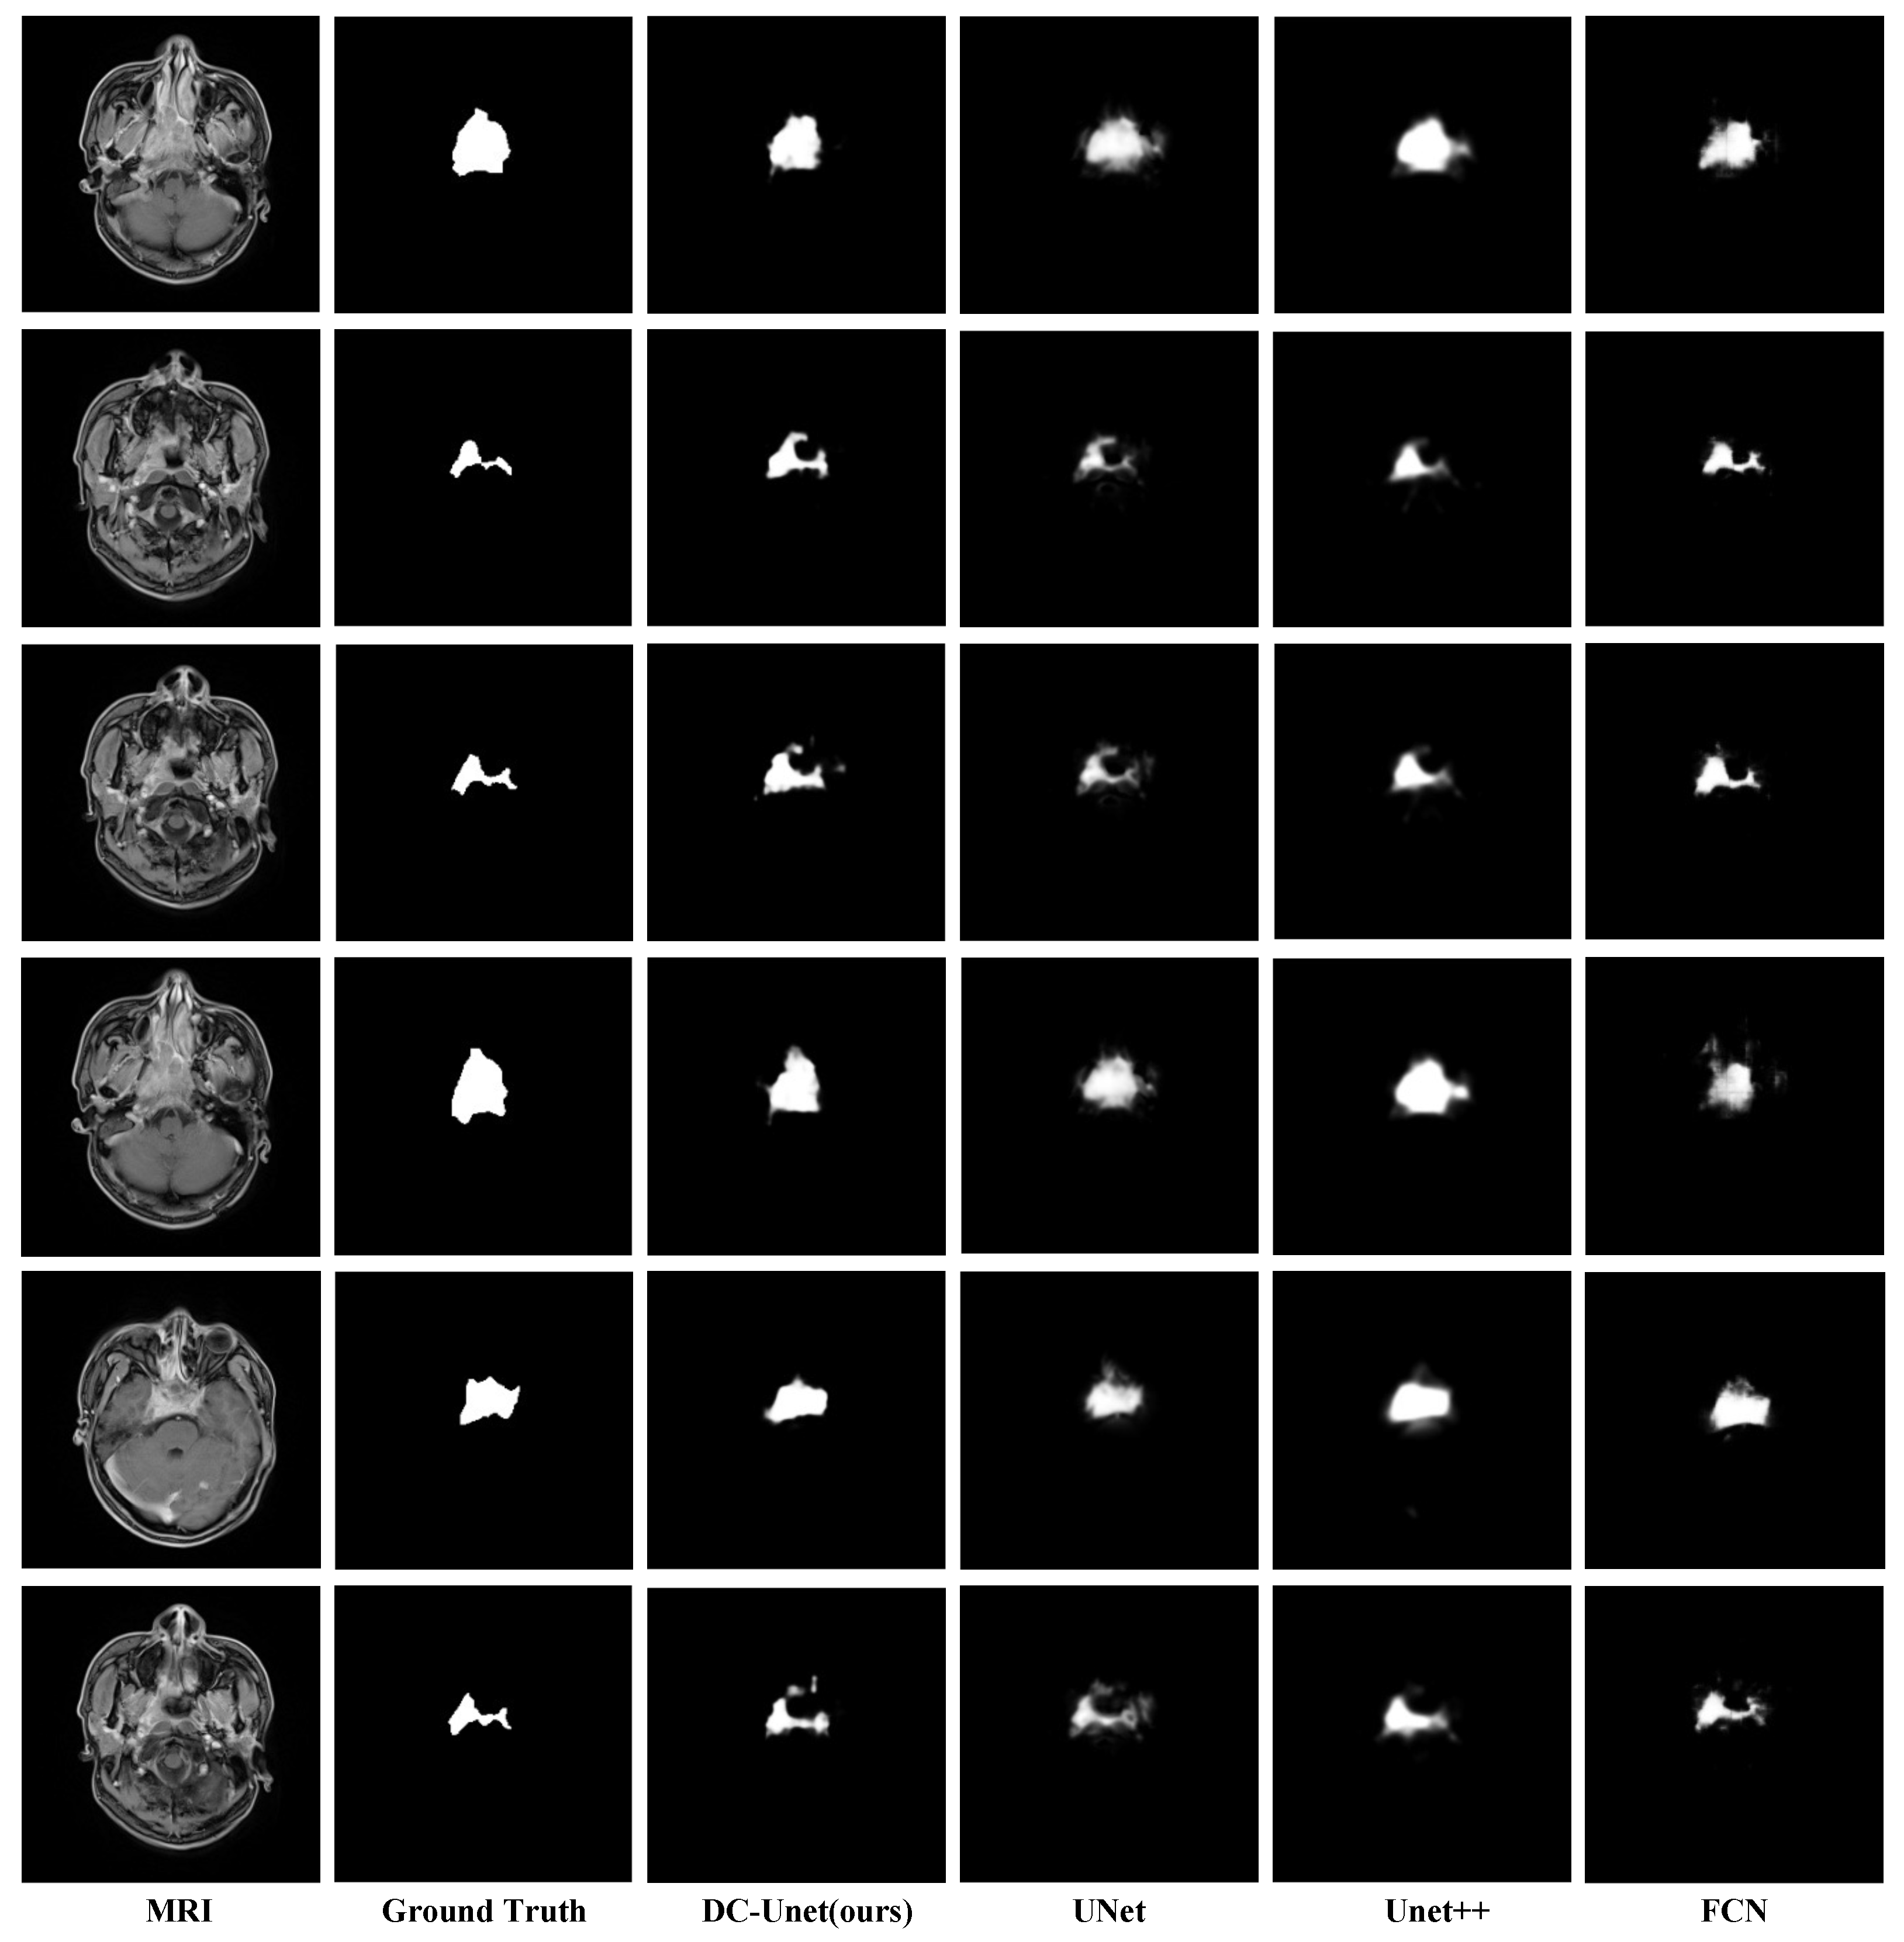

Figure 5 illustrates a visual comparison of segmentation results of tumors region with different sizes among DCNet and other baseline models. The results show our model performs better than the baseline models and gives a consistently precise result. Hence our model can handle the scale variation problem mentioned in Section 1.

Figure 5.

Visual comparison of segmentation results of DCNet and baseline methods. Please note that the segmentation results of our DCNet are more sharper when compared to U-Net and U-Net++. Additionally, the boundaries of the results of DCNet also fit ground truth better than the baseline models.